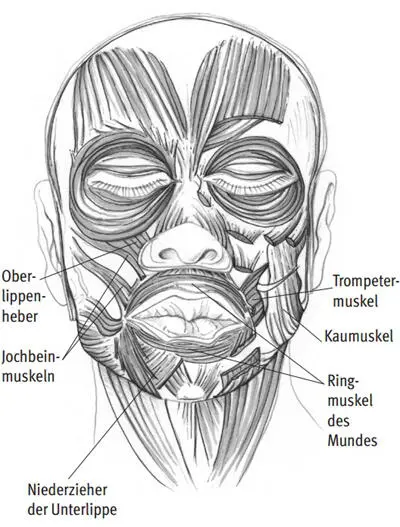

Für Bläser findet die Tonbildung am Übergang vom Vokaltrakt zum Instrument statt. Bei Holz- und Blechbläsern unterscheiden sich die physiologischen Vorgänge, welche zur Tonbildung führen. Gemeinsam ist jedoch allen Bläsern, dass zwischen Instrument und Spieler ein »Ansatz« gebildet werden muss. Dieser ist wesentlich von der mimischen Muskulatur – besonders den Lippen – und der Muskulatur des Vokaltrakts abhängig. Die komplex aufgebaute mimische Muskulatur zeigt Abb. I.59. Die physiologischen Vorgänge in der oberflächlich unter der Haut gelegenen mimischen Muskulatur lassen sich mit Oberflächenelektroden elektrophysiologisch untersuchen. Diese Art der Muskelfunktionsprüfung kann auch bei einer gestörten Funktion zu Trainingszwecken verwendet werden. 7

Abb. I.59: Mimische Muskulatur – Grundlage für die Ansatzbildung bei Bläsern